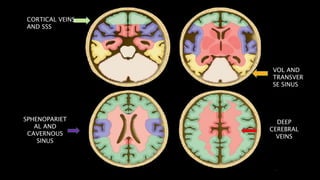

VENOUS

INFARCT

SPHENOPARIET

AL AND

CAVERNOUS

SINUS

DEEP

CEREBRAL

VEINS

VOL AND

TRANSVER

SE SINUS

CORTICAL VEINS

AND SSS

• #129 MIP image from CE MR venography with color overlay shows Lateral MIP images from CE MR V shows veins from the lateral cerebral hemisphere that drains into the SSS 1 frontopolar , 2 anterior frontal , 3 posterior frontal , 4 vein ot tolard , 5 anterior parietal 6 SMCV which drain into sphwenopartietal snus or cavernous sinus , 7 is the vein of labbe that drains into transverse sinus

• #130 These are the Axial color coded diag demonstrating venous draignage pattern. As we can see Most of the Superficial part of the brain ie. Cortex , subcortical white matter shown in green color atre drained by cortical vein ( including VOT) and sss. Central core brain structures ie basal ganglia , thalami , lat and 3rd ventricles and most of corona radiate are drained by deep venous system ie. ICB , VOG & SS. Transverse sinus and vein of labbe drain the posterior temporal and inferior parietal lobe as shown in yellow color . Sp and cv